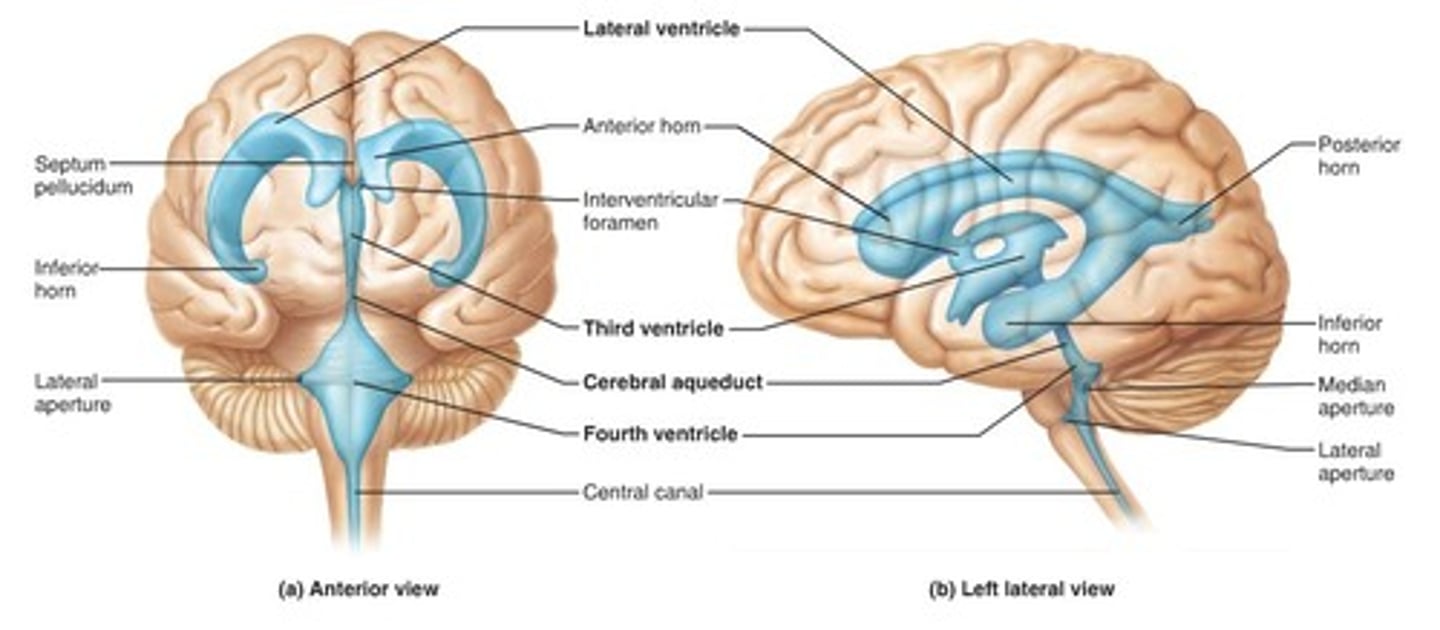

Ventricles

-Internal chambers within the brain

Lateral ventricles

-One in each cerebral hemispheres

-Interventricular foramen

Interventricular foramen

-Tiny pore that connects to third ventricle

Third ventricle

-Narrow medial space beneath corpus callosum

-Connects to cerebral aqueduct

Cerebral aqueduct

-Runs through midbrain and connects to third and fourth ventricles

Fourth ventricle

-Small triangular chamber between pons and cerebellum

-Connects to central canal that runs through spinal cord

Choroid plexus

-Spongy mass of blood capillaries on the floor of each ventricle

Ependymal

-Type of neuroglia that lines ventricles and covers choroid plexus

-Produces CSF

Cerebrospinal fluid

-CSF

-Clear, colorless liquid that fills the ventricles and canals of CNS

-Bathes its external surface